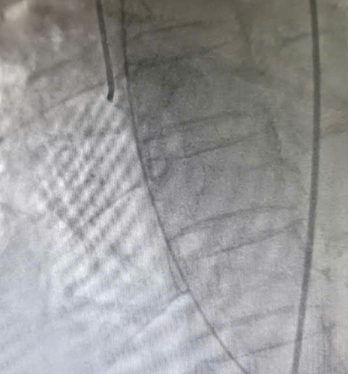

| Hình ảnh hệ động mạch vành không thấy hẹp tắc - Ảnh BVCC |

Mặc dù chụp mạch vành không phát hiện tổn thương tắc nghẽn, các bác sĩ tiếp tục quyết định chụp hình ảnh buồng tim. Kết quả cho thấy rối loạn vận động điển hình của hội chứng Takotsubo, với tăng co bóp ở đáy và giảm vận động ở mỏm tim, xác định đây là bệnh cơ tim cấp do căng thẳng.